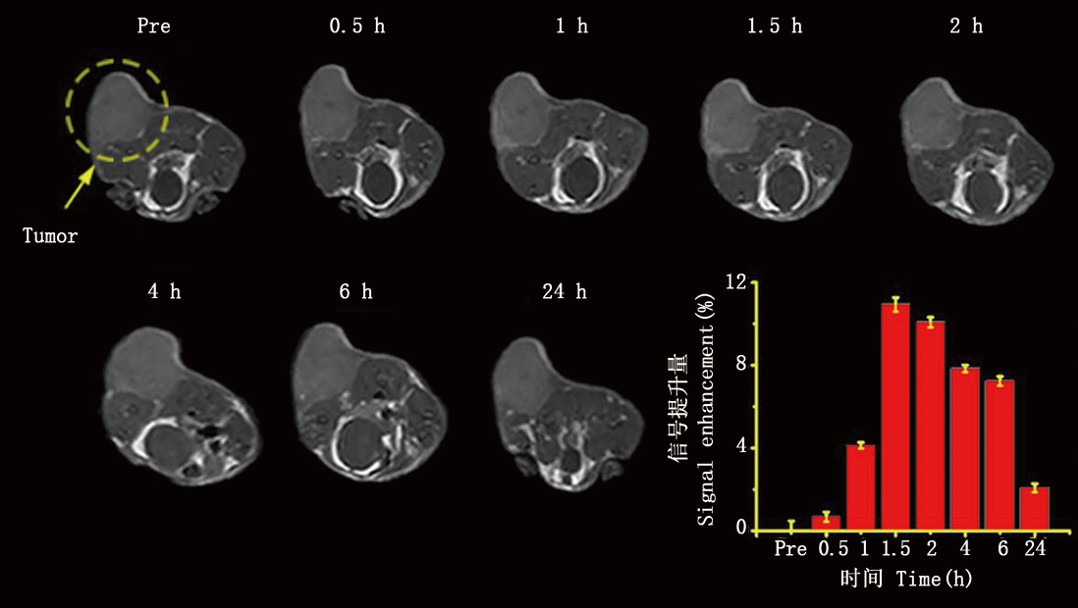

实验动物磁共振成像是在同种动物模型的情况下研究某些疾病的生物学和生理学特征的理想方法。实验动物磁共振成像还可以用于研究器官、肿瘤、血管和组织的结构和功能。

广泛应用:实验动物MRI成像广泛应用于心血管学、肿瘤学和组织工程学等域,提供了充足的信息和数据,有利于细致深入地研究生命科学问题。